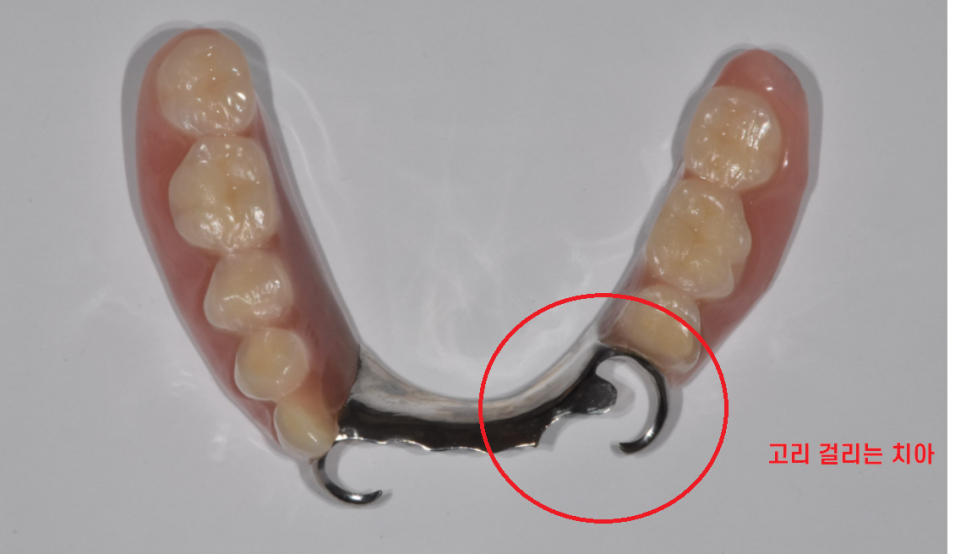

임플란트로 교체 하고나면

단순히 수술로 끝나서는 안됩니다.

일반적으로는 임플란트는 머리 완성 후

교합을 맞춰드리고 치료는 종결이지만

틀니 사용중 치아 부러짐으로

임플란트 치료를 하게되면

고리를 걸어서 사용하기 때문에

틀니가 잘 걸리게

기존 틀니를 수리까지 해주어야 완성됩니다.

틀니 수리까지 하여

편안하게 쓰실 수 있도록 치료를 끝내드렸습니다.